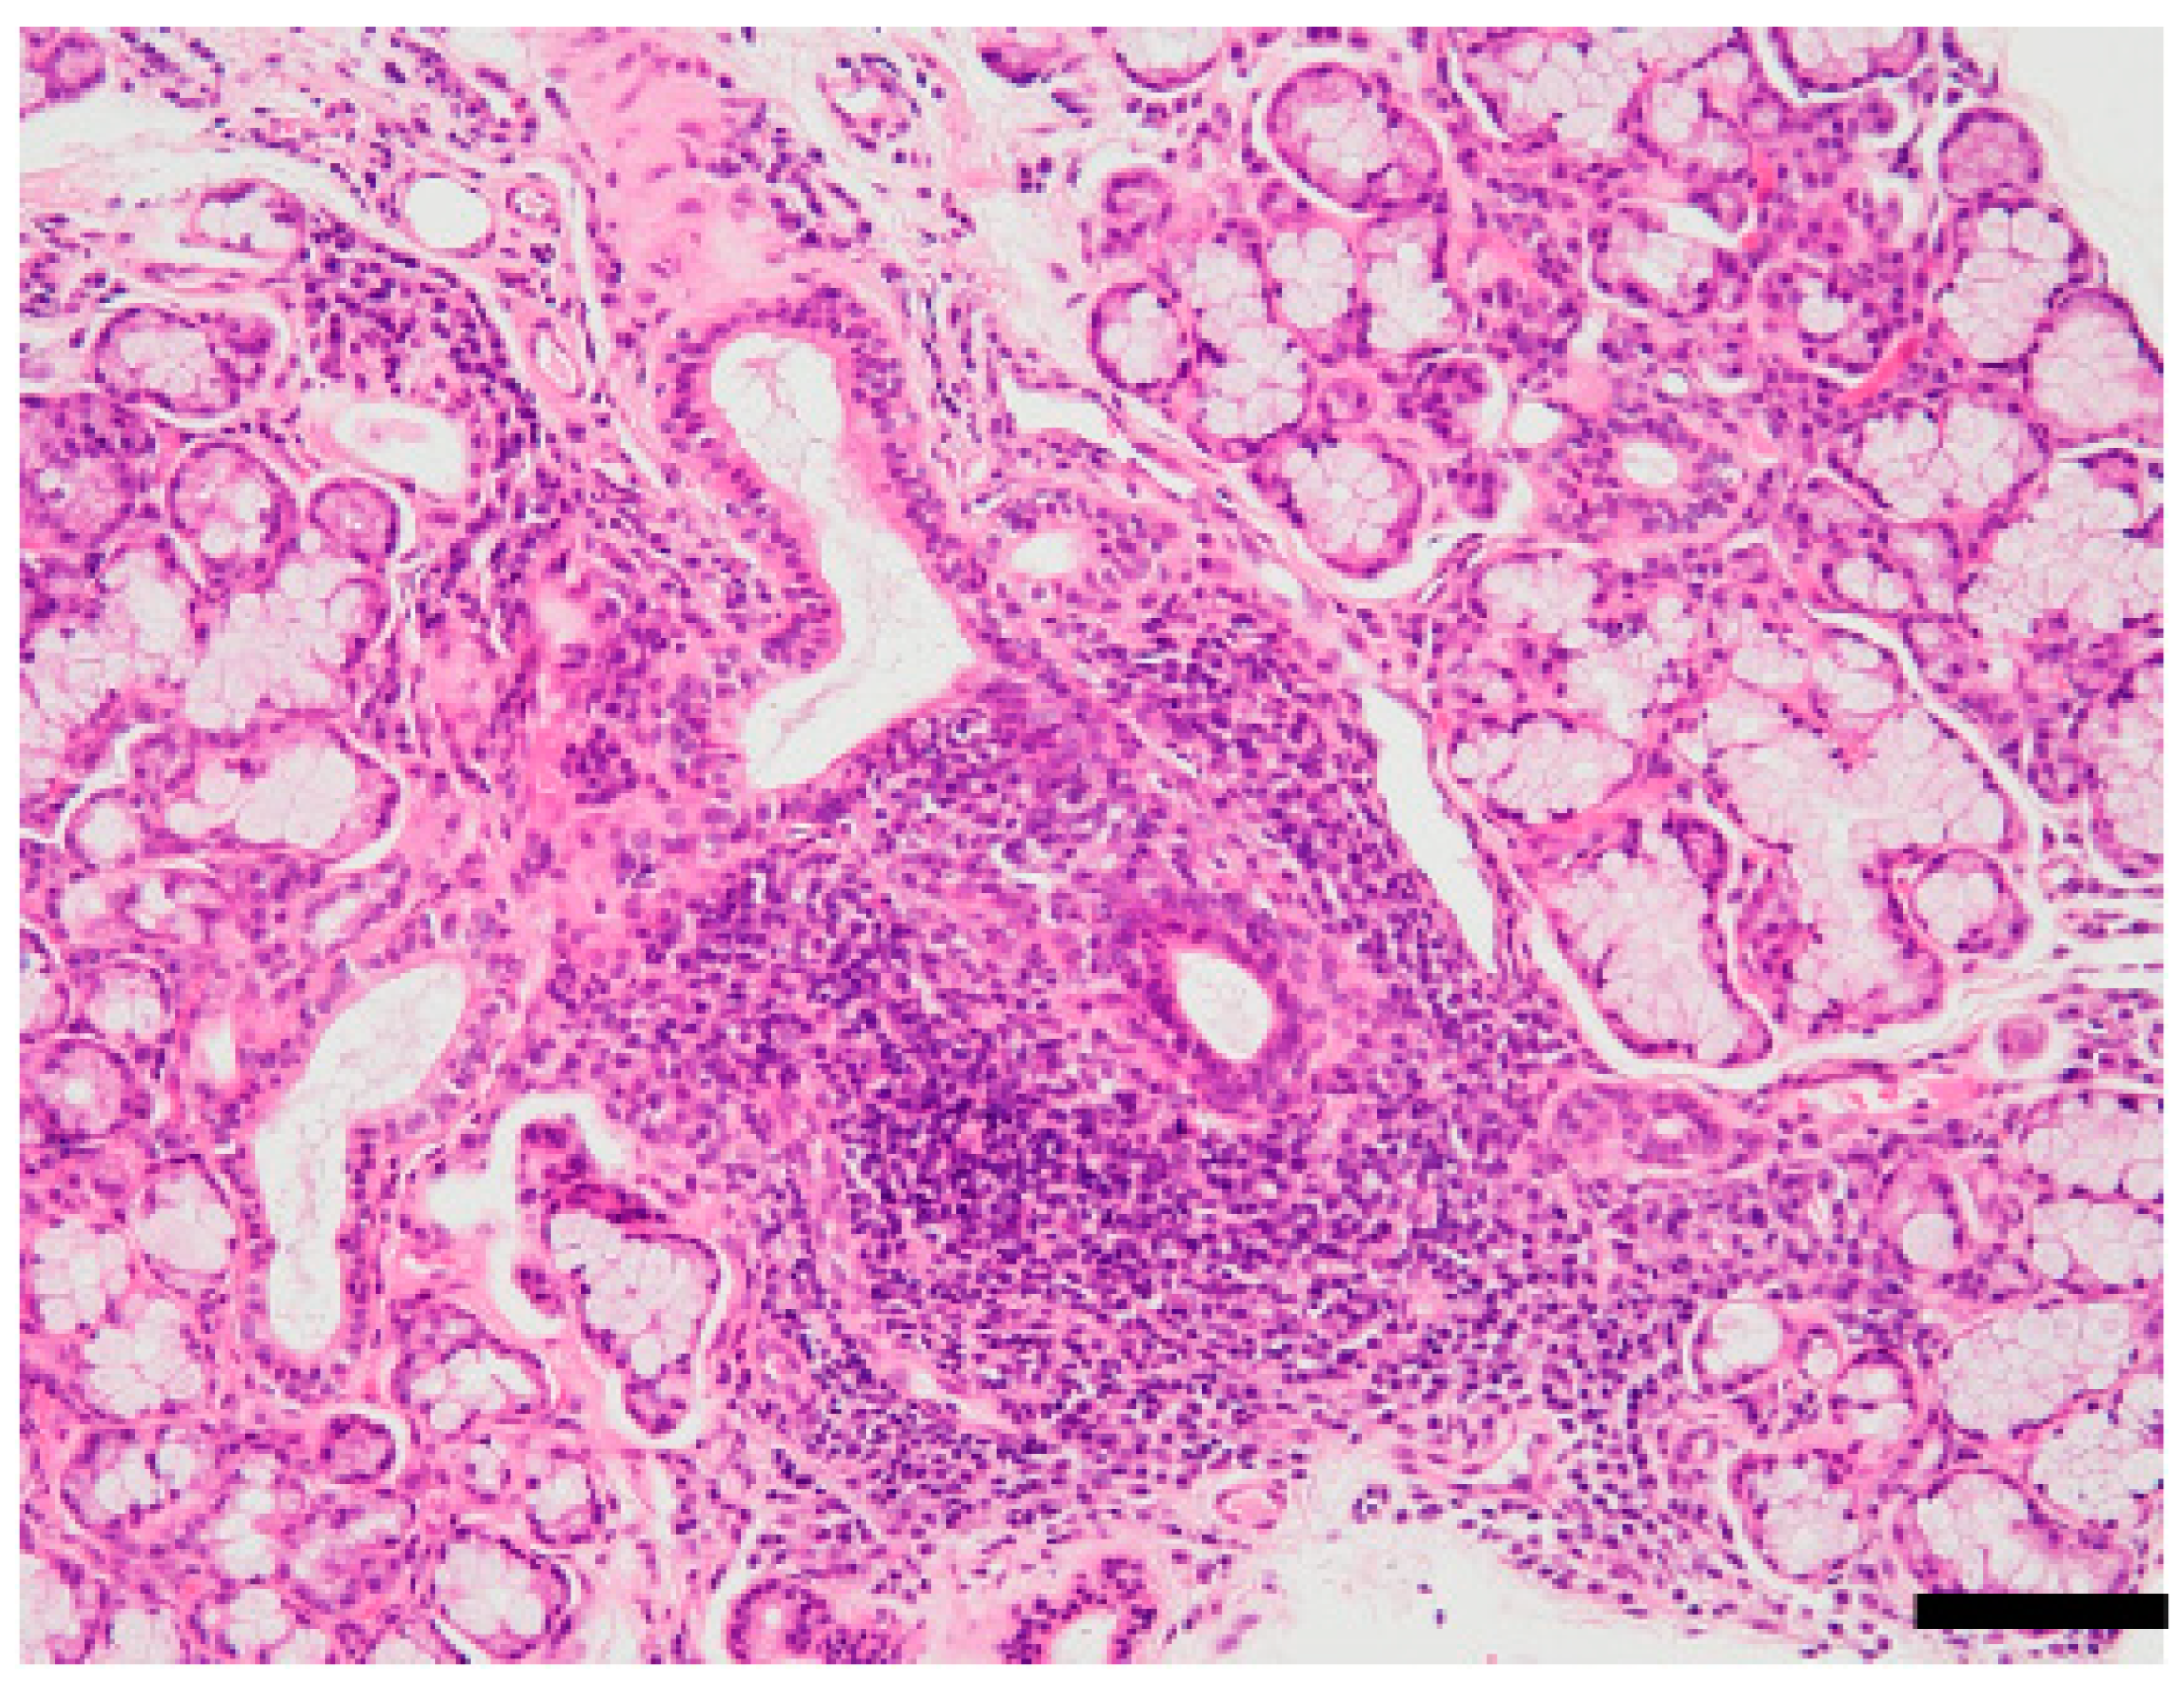

- Ishimaru, N.; Arakaki, R.; Yoshida, S.; Yamada, A.; Noji, S.; Hayashi, Y. Expression of the retinoblastoma protein RbAp48 in exocrine glands leads to Sjögren’s syndrome-like autoimmune exocrinopathy. J. Exp. Med. 2008, 205, 2915–2927. [Google Scholar] [CrossRef]

- Ishimaru, N.; Takagi, A.; Kohashi, M.; Yamada, A.; Arakaki, R.; Kanno, J.; Hayashi, Y. Neonatal exposure to low-dose 2,3,7,8-tetrachlorodibenzo-p-dioxin causes autoimmunity due to the disruption of T cell tolerance. J. Immunol. 2009, 182, 6576–6586. [Google Scholar] [CrossRef]

- Inoue, H.; Mishima, K.; Yamamoto-Yoshida, S.; Ushikoshi-Nakayama, R.; Nakagawa, Y.; Yamamoto, K.; Ryo, K.; Ide, F.; Saito, I. Aryl hydrocarbon receptor-mediated induction of EBV reactivation as a risk factor for Sjögren’s syndrome. J. Immunol. 2012, 188, 4654–4662. [Google Scholar] [CrossRef]